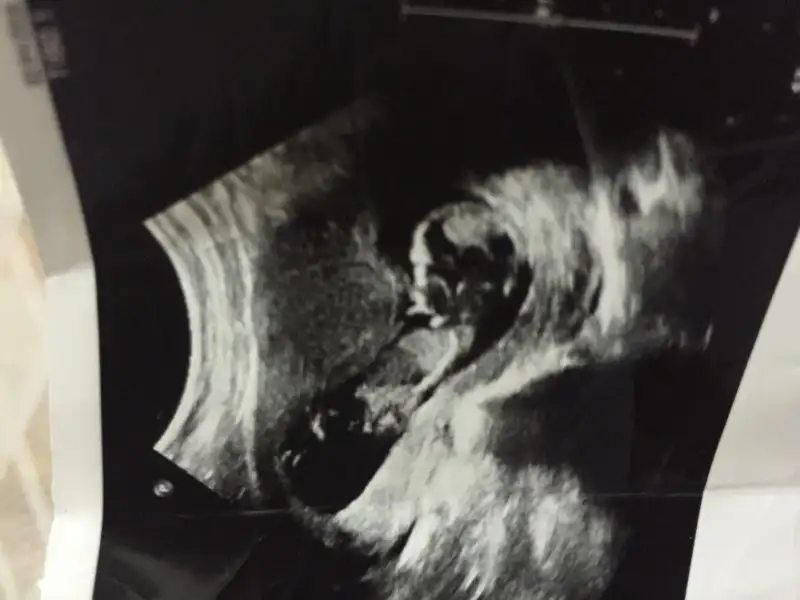

Plasentası sağda gözüküyor bu da gerçekte solda demektir. Ramzi teorisine göre kızı işaret eder. Allah sağlıkla kucağınıza almayı nasip eder inşallah

Teşekkür ederim Can'ım gönlümden geçen kız ne yalan söylim ama sağlıklı olması herşeyden önemli tabi Allah ne verdiyse baş göz üstüneErkek gibi cnm